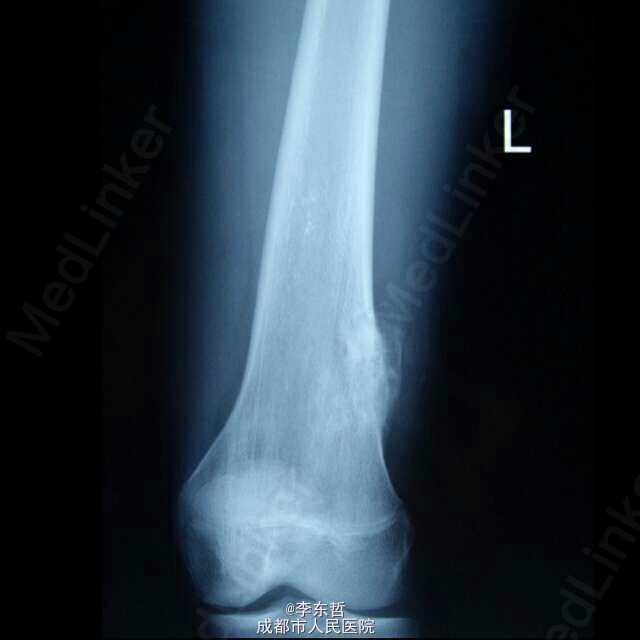

左股骨远端骨软骨瘤一例

患者男性,既往无异常,自诉左股骨远端处偶然触及无痛性肿块,当时未引起重视,一个月后来医院检查发现骨软骨瘤,遂行手术切除。